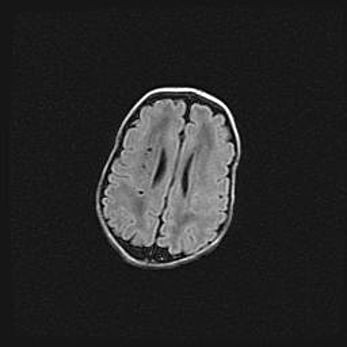

Лейкомаляция с кистозно-глиозной дегенерацией головного мозга.

Возраст: 2 месяца 25 дней

Вес: 6400 г

Окружность головы: 40 см

Срок гестации: 41 неделя

Лейкомаляцию относят к ишемически-гипоксическим повреждениям головного мозга, диагностируемым у новорожденных. При лейкомаляции в головном мозге обнаруживают очаги некроза, возникшие после тяжелой гипоксии и нарушения кровотока. В процессе морфогенеза очаги проходят три стадии: 1) развития некроза, 2) резорбции и 3) формирования глиозного рубца или кисты. Перивентрикулярная лейкомаляция (ПЛ) встречается примерно в 12% случаев среди новорожденных, обычно – у недоношенных детей, причем, частота ее зависит от массы, с которой младенец появился на свет. Наибольшее число малышей страдает лейкомаляцией, если масса при рождении 1500-2500 г.